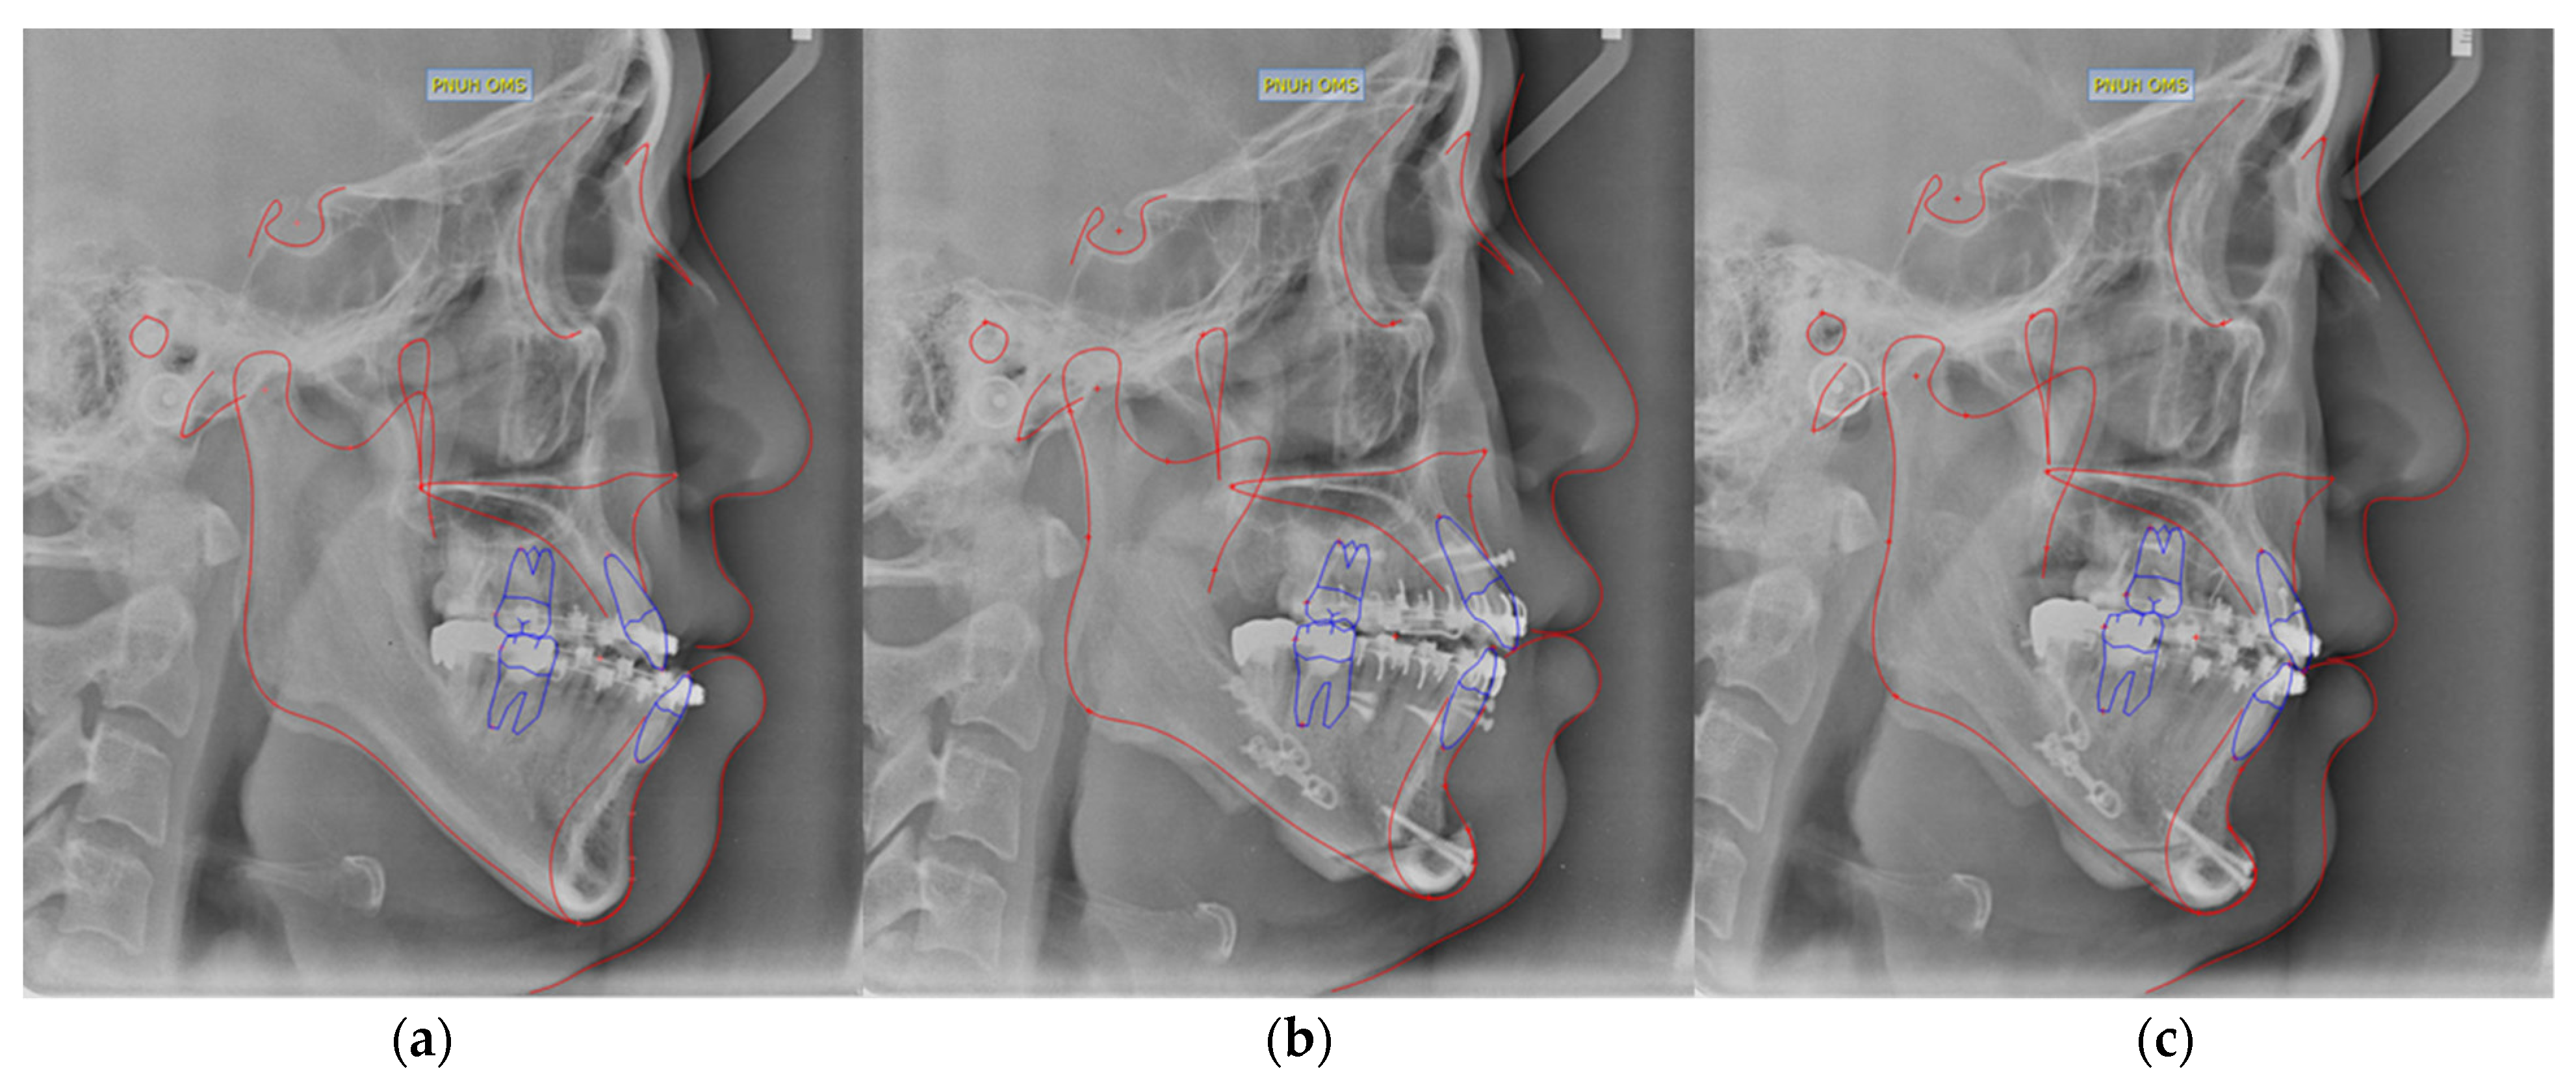

For all patients, cone beam computed tomography (CBCT), and lateral cephalometric radiographs were taken postoperatively on day 2 and month 6 to confirm skeletal changes (Figure 1 and Figure 2). Postoperative stability was evaluated and analyzed by measuring several measurement variables (L1 to NB, Pog. to NB, A-Pog., angle of facial convexity (AFC), SN vertical, and 0-merdian) (Table 1). The duration of each patient’s preoperative orthodontic period, the number of premolar extractions, and the number of impacted teeth were also compared and analyzed.

Figure 1. Orthognathic surgery patient with clear aligners. (a) Before surgery; (b) 2 days after surgery; (c) 6 months postoperative radiograph image. Braces attached to teeth were not observed on radiographs.